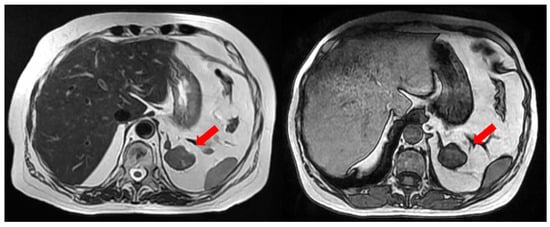

The bone mineral density (BMD) of the patient’s lumbar spine was first defined in 2022 with a T-score of −3.8 (Z-score −4.0, BMD 0.750 g/cm2), which was indicative of osteoporosis, leading to the initiation of treatment with denosumab. A magnetic resonance imaging (MRI) of the retroperitoneum performed as part of her investigation revealed a 3.5 cm lesion of the left adrenal gland with a suspicious morphology, not typical of an adrenal adenoma (Figure 2).

Figure 2. Abdominal MRI (T2–left and in/out of phase—right) depicting a 3.5 cm large left adrenal adenoma. Red arrows depict the left sided adrenal adenoma.